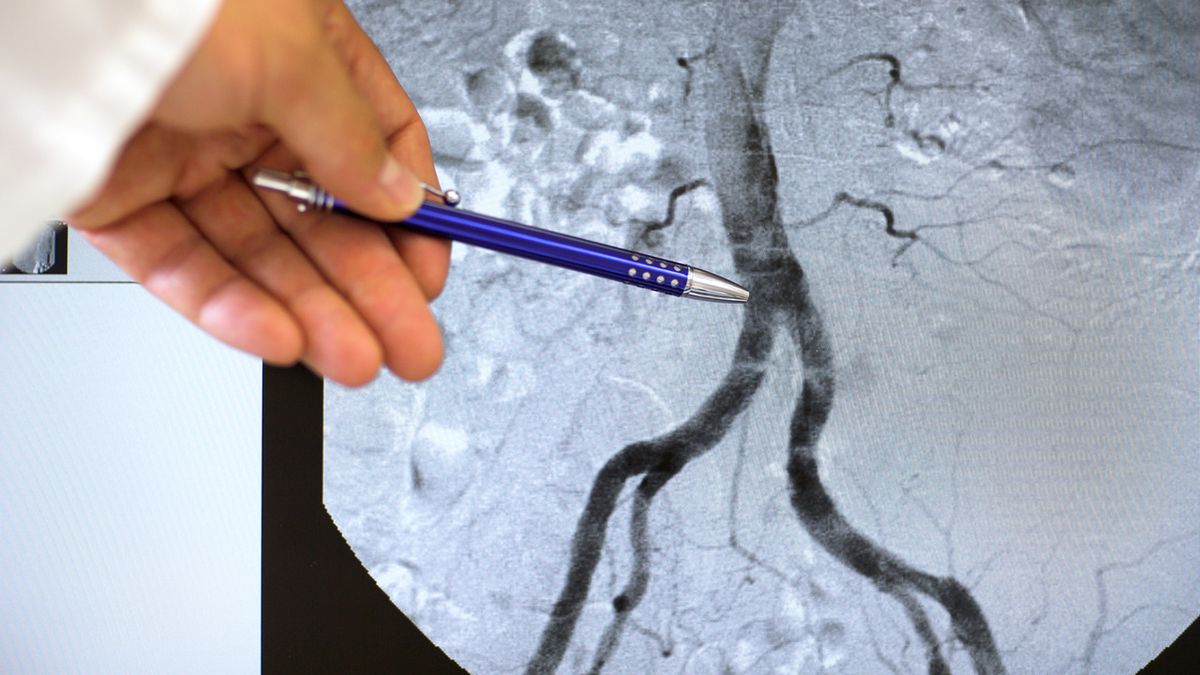

Choroby aorty mogą być wrodzone lub nabyte.Choroby aorty mogą być wrodzone lub nabyte.

Źródło zdjęć: © adobestock

Choroby aorty, czyli tętnicy głównej, mogą być niebezpieczne. Stanowią zagrożenie dla życia i zdrowia, ponieważ mają bezpośredni wpływ na inne narządy układu krążenia w tym na mięsień sercowy. Zaburzenia pracy aorty są również przyczyną zmian w całym organizmie. Schorzenia aorty dzieli się na wrodzone oraz nabyte.

W nieinwazyjnej diagnostyce obrazowej istotną rolę odgrywają: echokardiografia przezklatkowa (TTE) i przezprzełykowa (TEE), tomografia komputerowa (CT) oraz rezonans magnetyczny (MR). Leczenie często jest operacyjne.